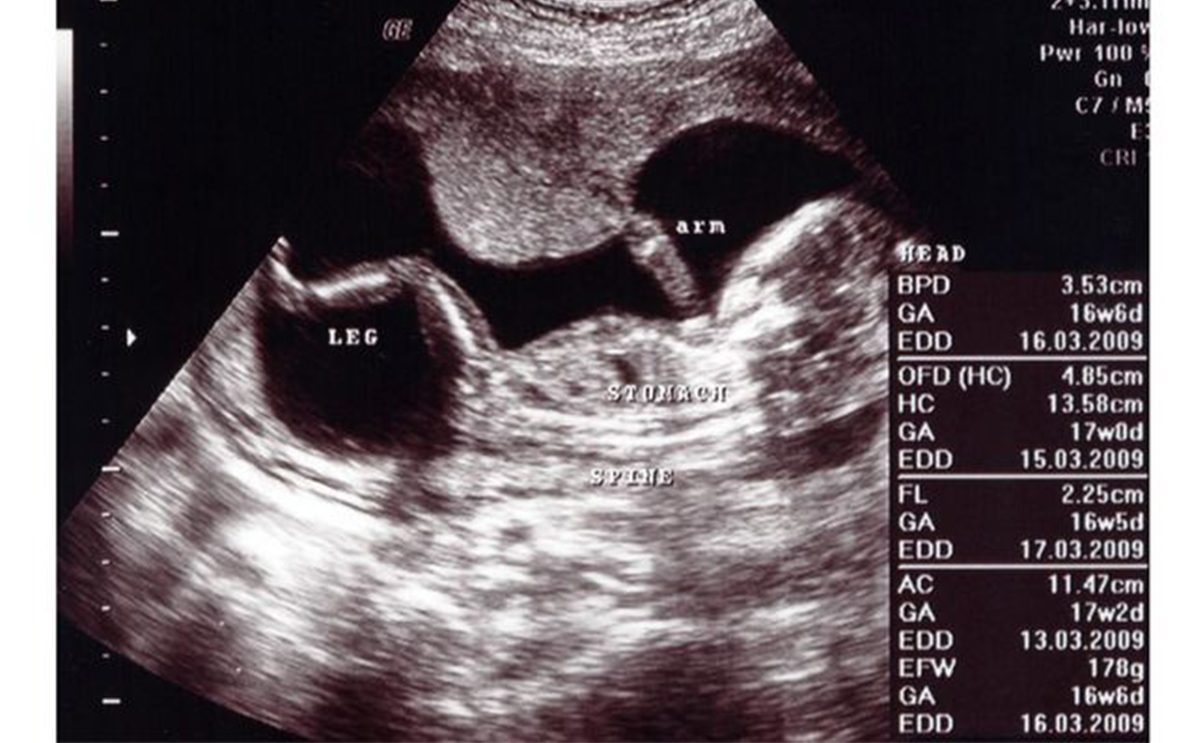

إن قراءة إختصارات السونار هي من الأمور التي تُهم المرأة الحامل وهذا كي تكتشف المعلومات بنفسها عن جنينها، ومن الأمور التي تهتم بمعرفتها هي وزن الجنين وكيف يمكن معرفته من ورقة السونار. ولقراءة وزن الجنين بورقة السونار، يظهر رمز "ewf" الذي يقدر هذا الوزن. أما رمز "ac"، فهو يُستخدم لمعرفة طول ووزن الجنين في مراحل الحمل المتقدمة والأخيرة وهو أيضاً يدل على محيط بطن الجنين.

رموز السونار

هذه هي باقي رموز السونار:

- Gn/gain: الظلال والضوء في الصورة.

- fh: قلب الجنين.

- pwr: قوة حزمة الموجات فوق الصوتية.

- ga: عمر الحمل.

- crl: طول الجنين وتقدير أو معرفة عمر الحمل.

- bpd: عمر الجنين ونموه الطبيعي.

- fhm: حركات قلب الجنين.

- x: يدل أن الجنين انثى.

- y: يدل أن الجنين ذكر.